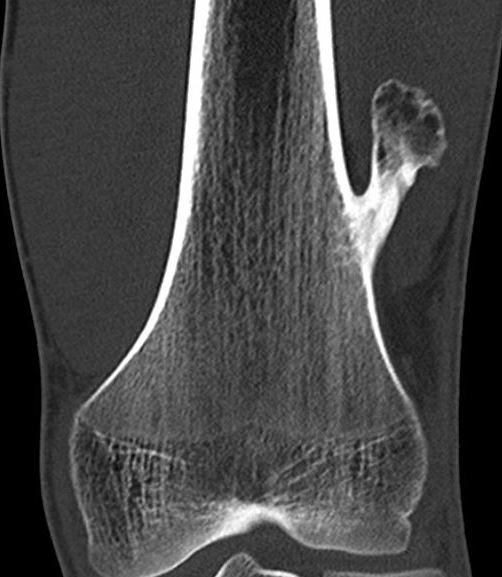

Malignant Transformation

Low-grade chondrosarcoma

- isolated lesion < 1%

- more common with central lesions

Suspicious features

- growth after maturity

- increased thickness of cartilage cap on CT / MRI - > 2 cm

- increasing pain

- increased calcification / bony erosion / lytic areas on xray

- septal enhancement after MRI with gadolinium

- MRI / CT of 64 benign osteochondromas and 34 secondary chondrosarcomas

- cartilage cap 2 cm or more 100% sensitive and 98% specific for secondary chondrosarcoma

CT

Cortex and medullary cavity of normal bone contiguous with osteochondroma